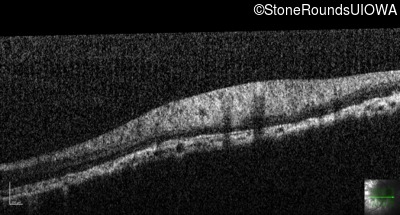

Optical Coherence Tomography - Left - 5/160

Exemplar / OCT Stack

OCT Stack